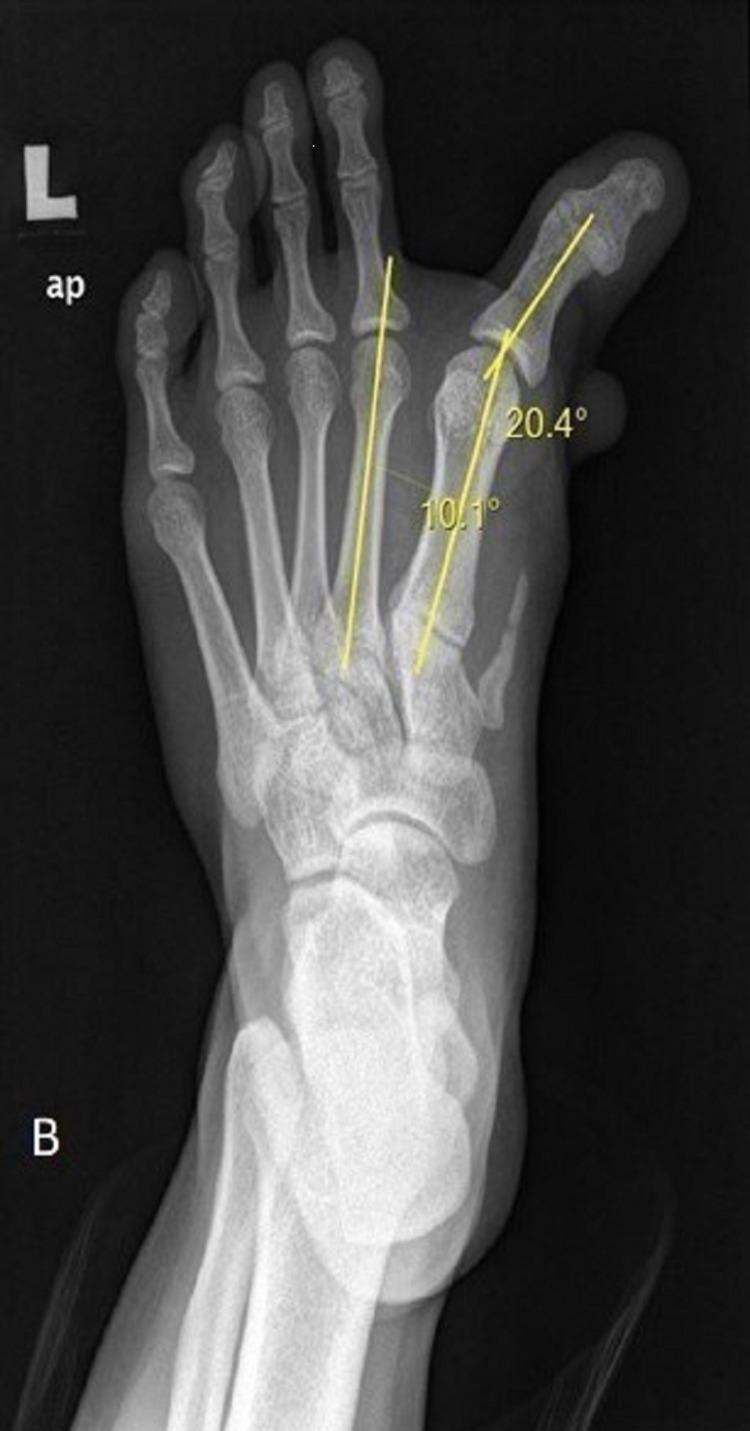

Congenital hallux varus is a rare forefoot deformity presenting with a deviation of the great toe medially. There are various techniques for the treatment of congenital hallux varus described in the literature. We present a case of a 16-year-old boy with congenital hallux varus who underwent corrective surgery, which involved soft tissue and bony procedure for better functional and clinical outcomes.

先天性拇内翻是一种罕见的前足畸形,表现为拇指向内侧偏斜。文献中描述了多种治疗先天性拇内翻的技术。我们报告一例16岁患有先天性拇内翻的男孩,他接受了矫正手术,该手术包括软组织和骨手术,以获得更好的功能和临床效果。